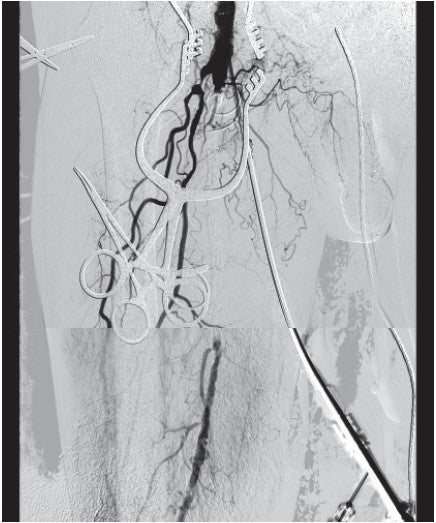

CFAおよびIliac領域治療後のSFA造影所見と石灰化の撮影では、閉塞長自体は150 mm程度だが、石灰化を伴う狭窄が連続しており、全体の病変長としては280 mmであった(図3)。

CFAを形成したパッチから順行性に7 Frのガイディングシースを挿入。5.5 Frのガイディングカテーテルを子カテとして用い、血管内超音波検査(IVUS)ガイドで0.014 inch ガイドワイヤーでワイヤリング。偽腔にずれる際は適宜別の0.014 inch ワイヤーでパラレルワイヤー法にて修正。石灰化の強い部分でワイヤー通過困難となったため、distal punctureを施行、表膝パンを行い、逆行性に0.014 inchガイドワイヤーとマイクロカテーテルを追従させた。最終的に逆行性からの0.014 inch ワイヤーを順行性からの5.5 Frガイディングカテーテル内にランデブーさせることに成功した。径3.0/長40 mmのハイプレッシャーバルーンにて拡張ののちIVUS確認。少なくとも中膜の内側でワイヤリングができていること確認。高度石灰化を伴うSFA CTOのCLTI症例であり、前拡張をしっかり行い十分な内腔を得た後に、バイアバーン® ステントグラフトでfull coverする方針とした。